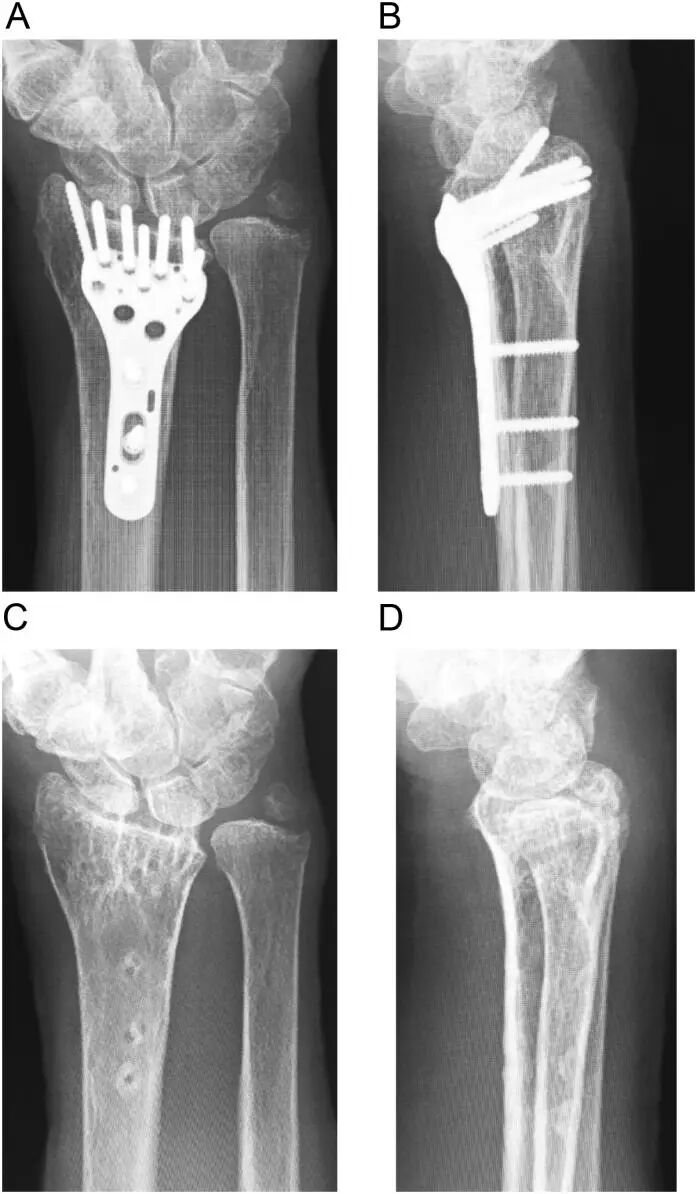

图2:术中C臂透视显示螺钉固定情况,尤其关注远端螺钉穿透背侧皮质以固定背内侧碎片。此图可能清晰显示了螺钉的长度和其与背侧皮质的关系,证实螺钉已穿透背侧皮质并突出。 -

此图可能为术后影像学检查,显示骨折复位良好,钢板和螺钉位置稳定,同时展示了突出螺钉在第三隔室中的情况,以及EPL肌腱已被安全处理后的良好效果。 - 在此病例中,手术进行至螺钉固定后,通过背侧小切口打开第三隔室。由于螺钉已穿透第三隔室并突出,我们按照上述方法将EPL肌腱从其凹槽中取出并通过缝合支持带来关闭隔室,确保肌腱远离螺钉,避免摩擦。